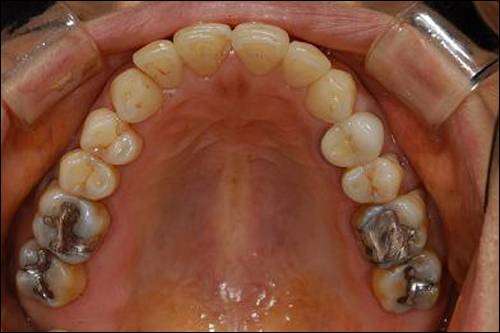

[치아 수복재 - 아말감] '경차' 수복재... 최대 장점은 '저렴함'

제일 먼저 살펴볼 아말감의 최대 장점은 역시 저렴함에 있다고 얘기하겠다. 그 밖의 장점으로는 치아의 상아질과 강도가 비슷해서 닳는 속도가 흡사하다는 점, 부식 시 발생하는 부산물에 의해 치면과의 사이가 잘 막혀서 미세누출이 적다는 점, 상대적으로 술자의 실력이나 환경의 영향을 적게 받는 점 등이다.

아말감의 단점은 일단 치아를 깎아야 하기 때문에 치질의 삭제가 많다. 실제로 환자의 치아는 위의 사진 모양으로만 썩은 것이 아니다. 아말감의 강도를 위해서는 썩지 않은 부분까지 삭제해서 위 사진과 같은 모양으로 형성을 해줘야만 한다.

다음으로 아말감 자체의 색이 좋지 않고 수복재 주변 치아를 변색시키기 때문에 비심미적이라는 단점 역시 가지고 있다. 마지막으로 인접치와 닿은 부분에서는 그 성능이 현저하게 떨어진다.